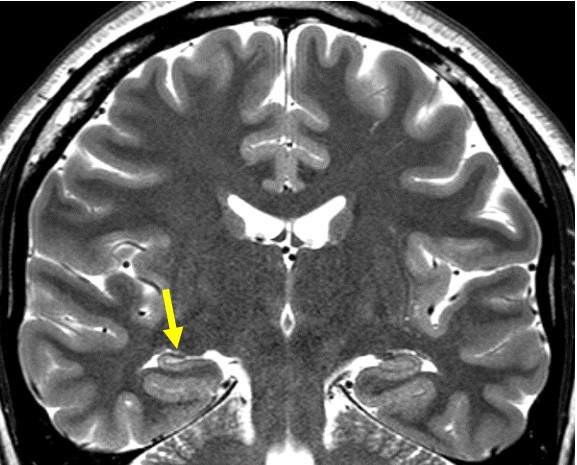

神経核内封入体病(NIID) 海馬硬化症

大脳の皮髄境界の高信号域 海馬の萎縮と高信号 T2強調像